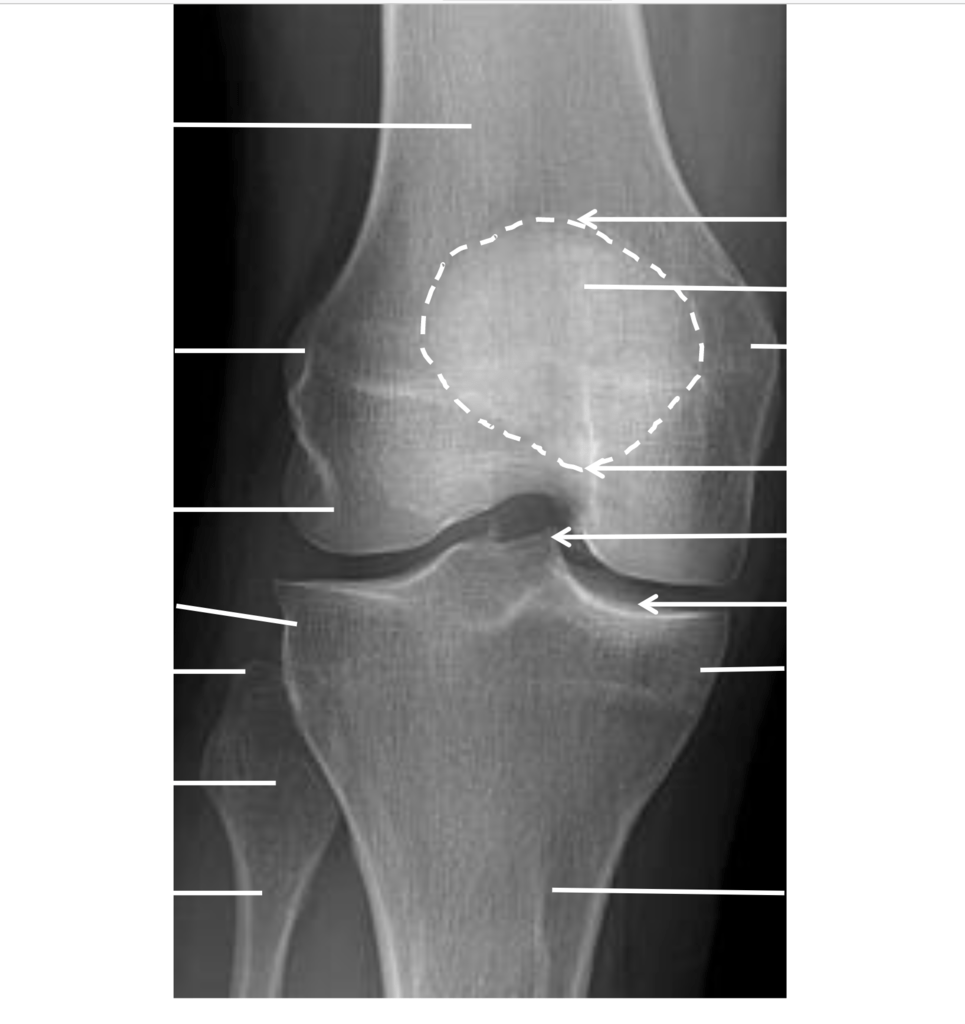

Normal Knee X Ray Anatomy What Can A Knee X Ray Diagnose while magnetic resonance imaging (mri) is widely. Knee joint space narrowing is a clinical sign of arthritis of the knee. This can help them diagnose osteoarthritis. a recommended systematic checklist for reviewing musculoskeletal exams is: Soft tissue areas, cortical margins, trabecular. What Can A Knee X Ray Diagnose.

Image What Can A Knee X Ray Diagnose Soft tissue areas, cortical margins, trabecular. Knee joint space narrowing is a clinical sign of arthritis of the knee. while magnetic resonance imaging (mri) is widely. This can help them diagnose osteoarthritis. a recommended systematic checklist for reviewing musculoskeletal exams is: What Can A Knee X Ray Diagnose.

AP Knee XRay Labeled Diagram Quizlet What Can A Knee X Ray Diagnose a recommended systematic checklist for reviewing musculoskeletal exams is: Soft tissue areas, cortical margins, trabecular. Knee joint space narrowing is a clinical sign of arthritis of the knee. This can help them diagnose osteoarthritis. while magnetic resonance imaging (mri) is widely. What Can A Knee X Ray Diagnose.